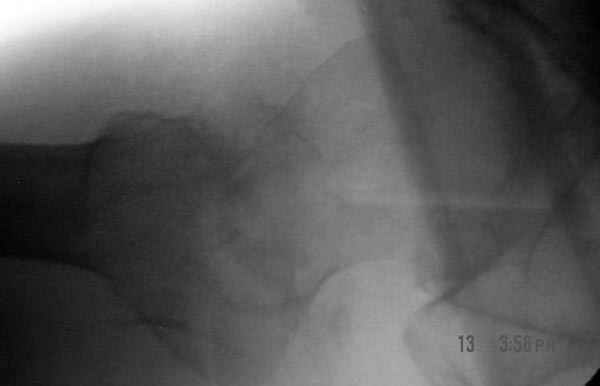

Другие случаи: применение Synthes TTFN (trochanteric titanium femoral nail) и Blade Plate (угловая пластина), так что много различных вариантов фиксации подобных переломов.